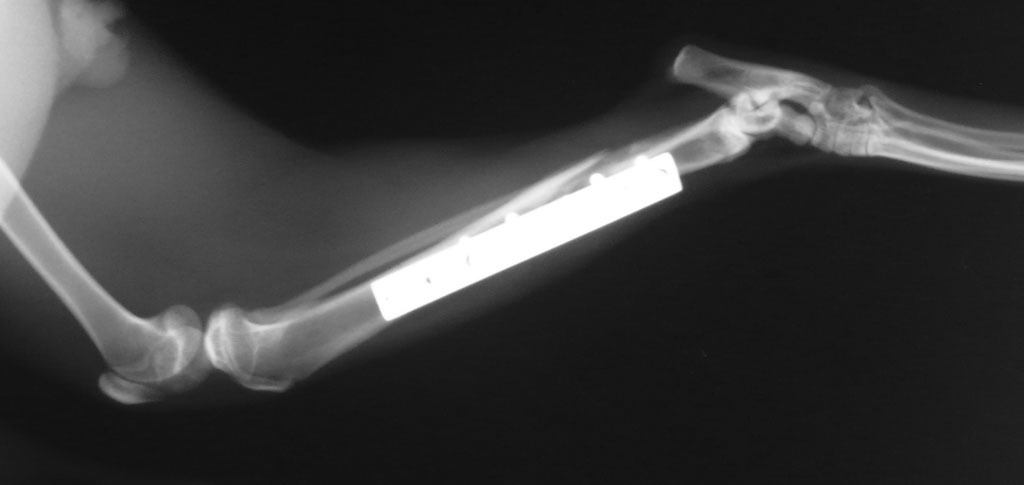

過兩天,抓到牠了,送到長沁醫院。麻醉完,張醫師打開牠的嘴一看,四顆犬齒全爛了,犬齒旁還有一個婁管(一個大洞),氣味非常不好聞,可見裡面已經嚴重發炎了,張醫師說,如果沒有及時處理,未來有可能會敗血症而死亡。之後照了x光,發現牠的後腿骨折了,需要馬上動手術處理。當天,晚上八點多我去醫院看牠,張醫師還在縫合傷口,手術時間頗長。

目前橘子貓骨折部分已完全癒合,已出院暫住中途家休養,待皮毛完全長出後,會原地野放照顧。